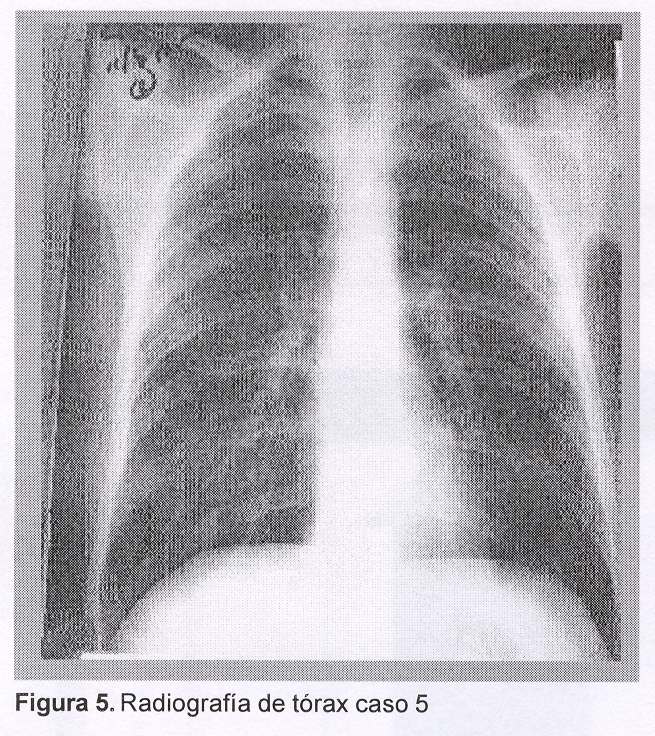

Caso 5. Hombre, 53 años, vive en asentamiento. Contacto con roedores, vivienda y terreno inundables. Consultó por fiebre, mialgias, disnea progresiva y expectoración hemoptoica de cinco días de evolución, encontrándose al examen pulmonar estertores crepitantes difusos bilaterales. Radiografía de tórax: opacidad de aspecto exudativo con broncograma aéreo, en mitad inferior de ambos campos pulmonares (figuras 5). Tomografía axial computarizada de tórax (figura 6). Gasometría arterial, máscara de flujo libre: pH=7,41, pCO2=21 mmHg, pO2=71 mmHg, Sa O2=94%, –HCO3=23 mmol/L, BE=1,3 mmol/L. Ingresó a cuidado intermedio para asistencia respiratoria no invasiva. Hemograma: glóbulos blancos 8.400/mm3, hemoglobina 13g/dL, plaquetas 468.000/mm3. Azoemia=1,46 g/L, creatininemia= 2,73 mg/dL. Funcional hepático: bilirrubina total 0,94 mg/dL, TGO 32 mU/mL, TGP 28 mU/mL. Serología para leptospira, MAT: títulos primera muestra, serovares Icterohemorra-giae/Copenhageni 1/800, Semaranga/Patoc 1/400.